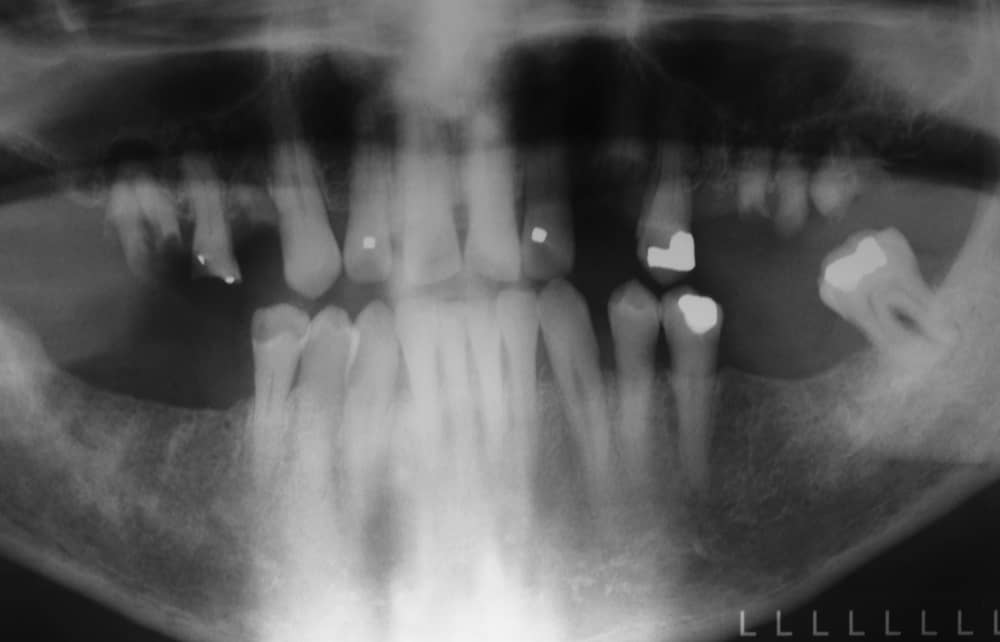

Before: Failed upper remaining teeth requiring removal. Patient elected to proceed with Phase I immediate complete denture therapy with the view toward phase II implant therapy.